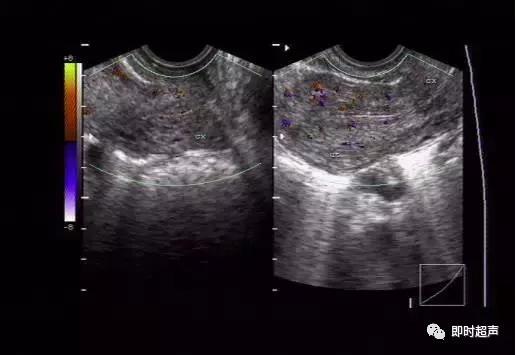

正常子宫及宫颈血流图